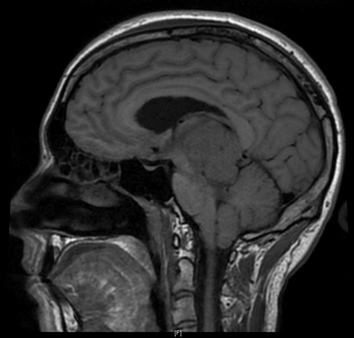

Céphalées, perte de poids chez un jeune adulte

Cas Clinique

Source : NeuroScoop.net - Actu'Hebdo janvier 2018

Dr Victor Basse CHRU Brest - Brest

- Patient de 24 ans sans antécédents particuliers.

- Depuis environ 10 mois, vomissements matinaux soulageant des céphalées frontales dans un contexte de perte de poids.

- Syndrome cérébelleux statique.

- Diplopie horizontale binoculaire, nystagmus, paralysie de la verticalité...